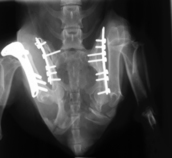

This was a challenge; a young dachshund who had a serious road accident leaving her pelvis in pieces and and a broken femur

It took 3 seperate operations to fix her pelvis and femur. She has now made a full recovery and is running around on Filey beach!